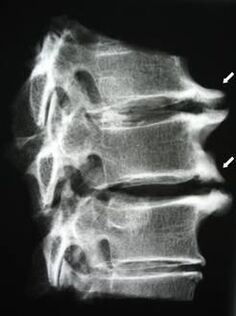

В началните етапи остеохондрозата се открива с помощта на ЯМР. По-късно патологията може да бъде диагностицирана с помощта на радиография. На рентгенографията на шийния отдел на гръбначния стълб се забелязва намаляване на разстоянието между прешлените, патологични промени в фасетните стави и остеофитоза.

| Цервикална остеохондроза | Появата на патологични промени в един или повече гръбначно-двигателни сегменти. Нарушена подвижност на гръбначния стълб, развитие на миофасциални болкови синдроми и прищипване на гръбначните корени | Болка, парестезия и двигателни нарушения в цервикалната област, които се разпространяват в задната част на главата и горните крайници. Откриване на характерни промени в гръбначния стълб при ЯМР и рентгенови снимки (остеофити, намалено разстояние между прешлените, признаци на увреждане на междупрешленните стави) |